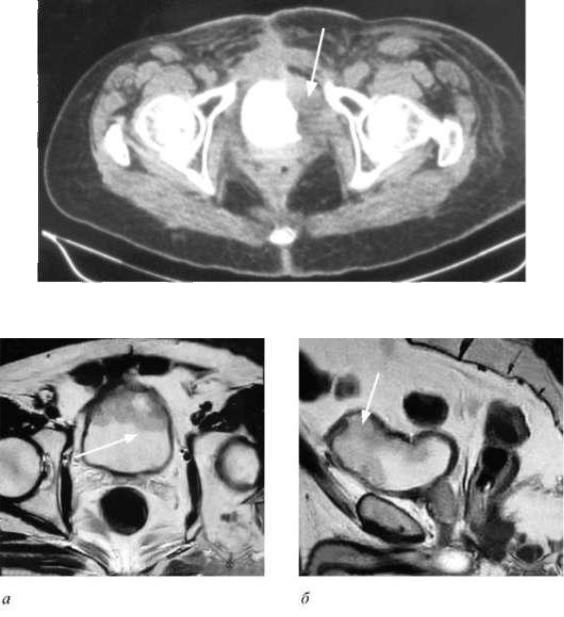

Изображения КТ конкрементов мочевого пузыря